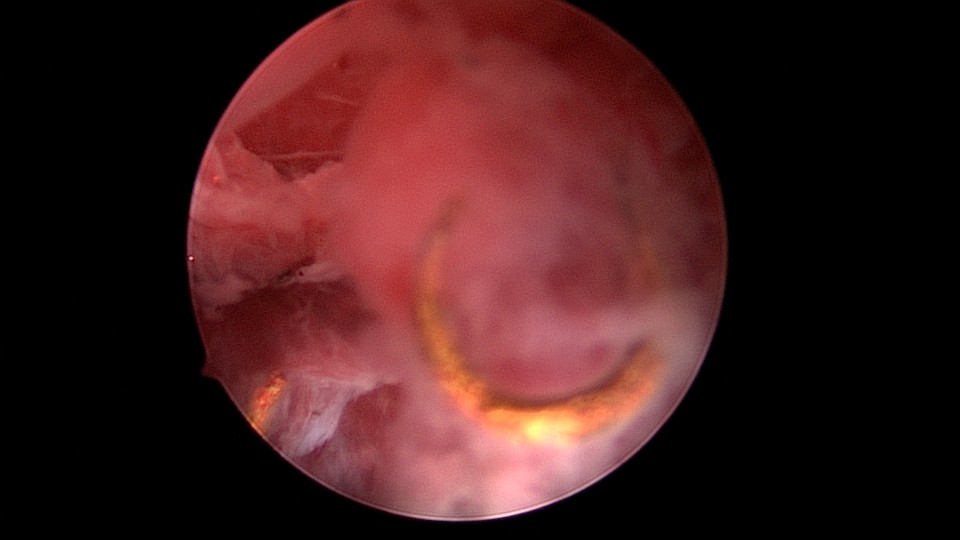

患者49岁,G1P1,顺产1次。安环13年,月经紊乱1月,外院取环失败。B超提示O型环嵌顿,宫腔镜见宫颈管及宫腔组织充血,宫腔广泛粘连,节育环嵌顿、扭曲,异物钳配合中弯钳拉出节育环,环变形、断裂,宫壁节育环嵌顿处见割裂痕迹,无出血,检查宫腔各部,无节育环残留。